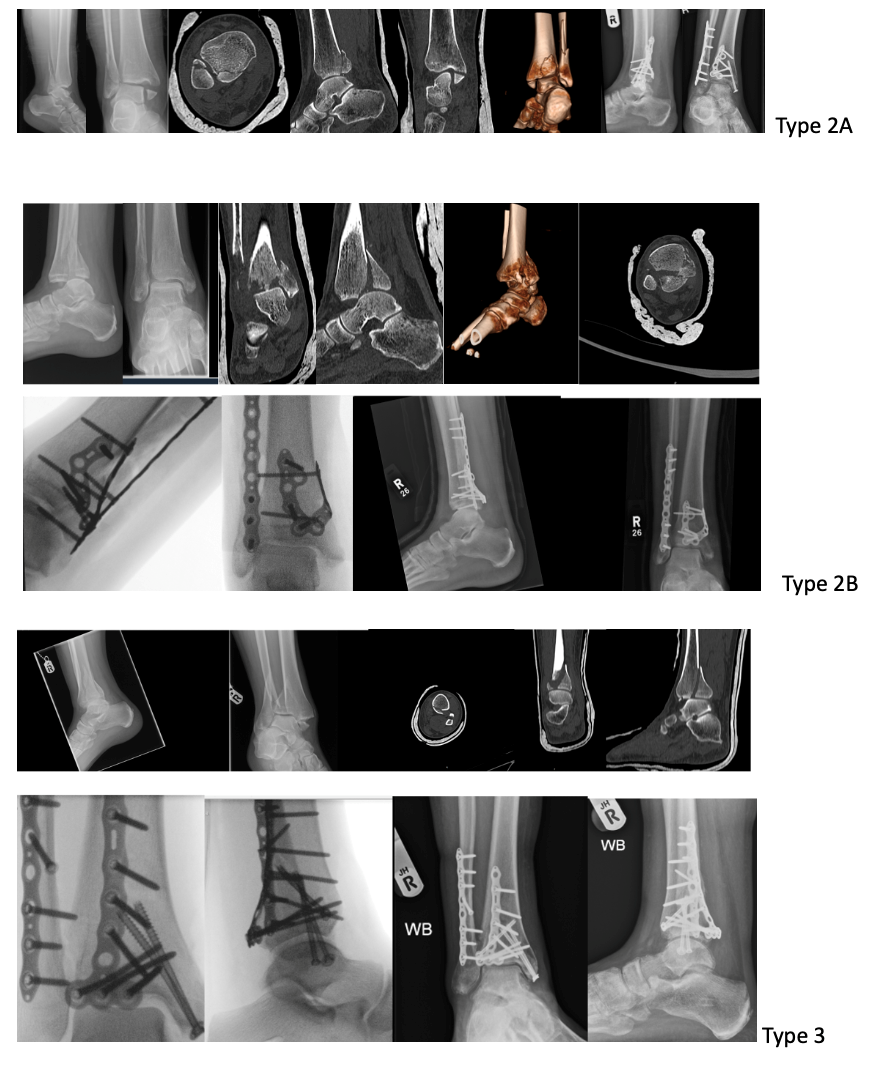

Management of bimalleolar fracture is quite standard however when it comes to trimalleolar fracture, management of posterior malleolar fragment has notable variability in surgeon’s practice. Access to the advance imaging helps better understanding of fracture’s configuration and planning (Fig1). Different approaches and techniques have been described to address these fractures. In this Study we looked at these fractures treated with fragment specific fixation and reported functional and radiological outcome.

Fig 1 Radiographs and CT scan demonstrating different patterns of trimalleolar fractures.

All patients presented to our department with trimalleolar ankle fractures from October 2021-March 2023 were included in the study. We excluded the patients from study who were under 18 years of age, does not require posterior malleolus fixation or need fixation method other than plate osteosynthesis. On presentation trimalleolar fractures were identified on Anterior-posterior and lateral radiographs. Patient presented with subluxation or dislocation of ankle needing manipulation were treated by the on-call team Post reduction Splinting (Back slab) was applied and radiographs were obtained to assess the reduction. Subsequently computed tomography (CT) was acquired with coronal, sagittal, axial planes, and 3D reconstruction. The fracture fragments were evaluated using Mason & Molloy classification14 and divided into subtypes 1, 2a, 2b and 3 fractures (Fig 2). Definitive fixation was delayed until the soft tissue settles. If concern with soft tissue and unstable fracture not able to maintain the position in back slab, temporary external fixation was applied until soft tissue settles. Osteosynthesis using fragment specific implant (VolitionTM) and relevant surgical approach was performed. Post operatively these patients were followed in outpatient department at 2, 6,12,26 weeks. They were clinically assessed for any pain, stiffness, infection, nerve damage, CRPS metalwork irritation or failure, and clinical union Functional assessment was carried out using The Manchester-Oxford Foot Questionnaire (MOXFQ) and Foot and ankle disability index (FADI). Anterior -posterior, lateral and mortise radiographs were taken to assess the fixation, adequacy of reduction and radiological union.

The Patient position and surgical approach to address these fractures was guided by fracture configuration and surgeon’s preference. Wherever possible we addressed the posterior malleolus fracture first and used the relative fragment specific implant. It allows the better radiographic visualisation of reduction and no interference from metalwork. This is followed by lateral   malleolus fixation when fixing 2a fractures but in type 2b fractures, medial malleolus fracture was fixed before the lateral fragment stabilisation and in Type 3 sequence of fixation was dependent on type surgical approach. (Fig 4)

Fig 4 Showing Pre-op and post op Imaging of different trimalleolar fractures and their fixation using fragment specific Plates.